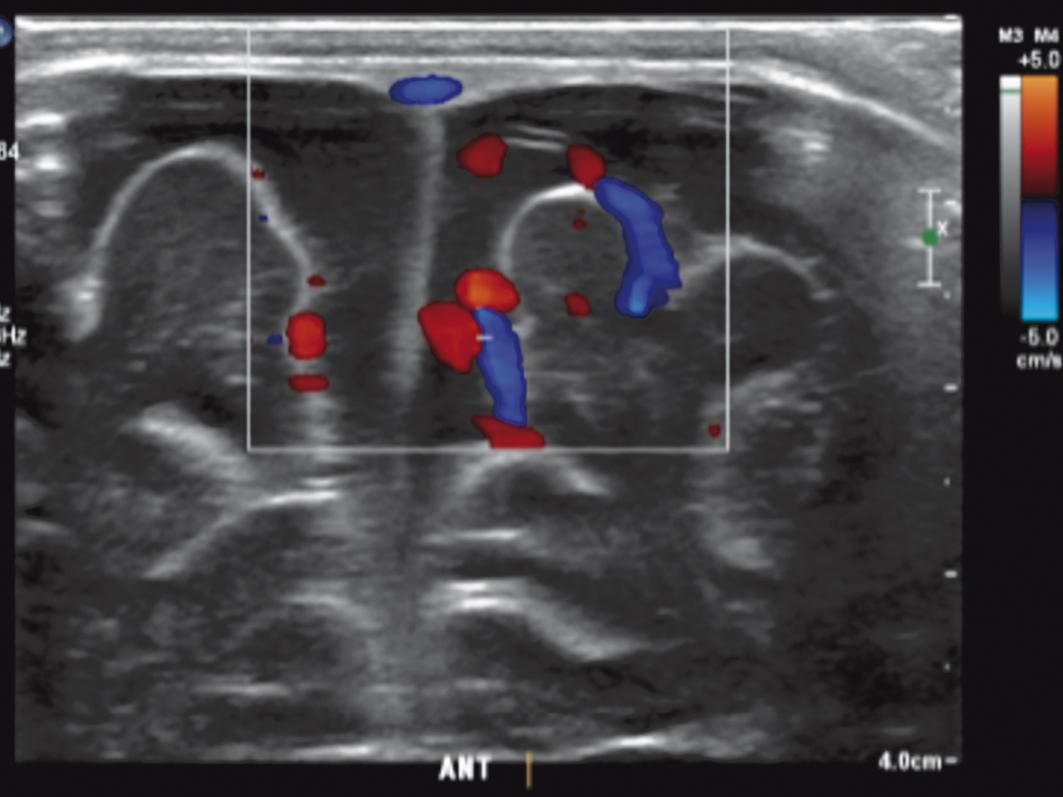

O método ainda serve para acompanhar crianças que foram submetidas a procedimentos cirúrgicos para o tratamento da ventriculomegalia, como a derivação ventriculoperitoneal (DVP), já que avalia os ventrículos (figura 5) e detecta precocemente as possíveis complicações, a exemplo de obstrução da DVP e de sinais de hipertensão intracraniana, observados com a complementação da avaliação vascular.

Figura 5. Corte coronal aponta ventrículos laterais dilatados, com presença de cateter de derivação ventriculoperitoneal.